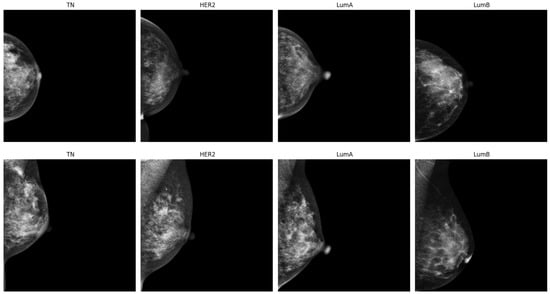

2.1. Dataset

- Cai, H.; Wang, J.; Dan, T.; Li, J.; Fan, Z.; Yi, W.; Cui, C.; Jiang, X.; Li, L. An online mammography database with biopsy-confirmed types. Sci. Data 2023, 10, 123. [Google Scholar] [CrossRef] [PubMed]